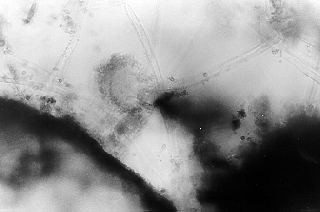

Indoor air in dwellings. In the USA, the Aspergillus sp. fungus was found in 9 - 29 % and in Scotland in 74 % of the examined homes. In Ontario, Canada, their concentration in the air of dwellings was 22 cfu/m3. In Slovakia, Aspergillus sp. strains were isolated from 9 %, A. flavus from 30 % ( 5 % of strains were able to produce alflatoxins B1, B2, G1 and G2 in vitro), Aspergilli from the group of A. glaucus from 2 %, A. ochraceus from 12 %, Aspergilli from the group of A. restrictus from 2 % and A. ustus from 5 % of examined "moldy" dwellings. Microscopic pictures of scrapings from walls and wooden window frames of some houses are presented (Fig. 1-4) (Piecková et al., 1999).

Fig 1. Scraping from a wall in a nursery - a fragment of a fruiting body of A. versicolor type (magn. 1000x).

Fig 2. Scraping from a wall in a fitness room - a fruiting body of Aspergillus sp. type (magn. 200x).

Fig 3. Home dust - a fruiting body of A. versicolor (magn. 400x).

Fig 4. Scraping from the window frame in a fitness room - a fruiting body of Aspergillus sp. type (magn. 400x).